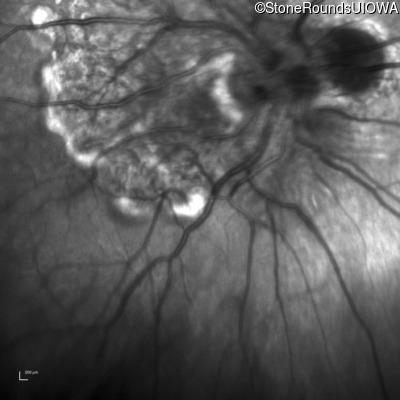

Infrared Fundus Photograph - Right - 20/400

Exemplar

Infrared Fundus Photograph - Left - 20/100